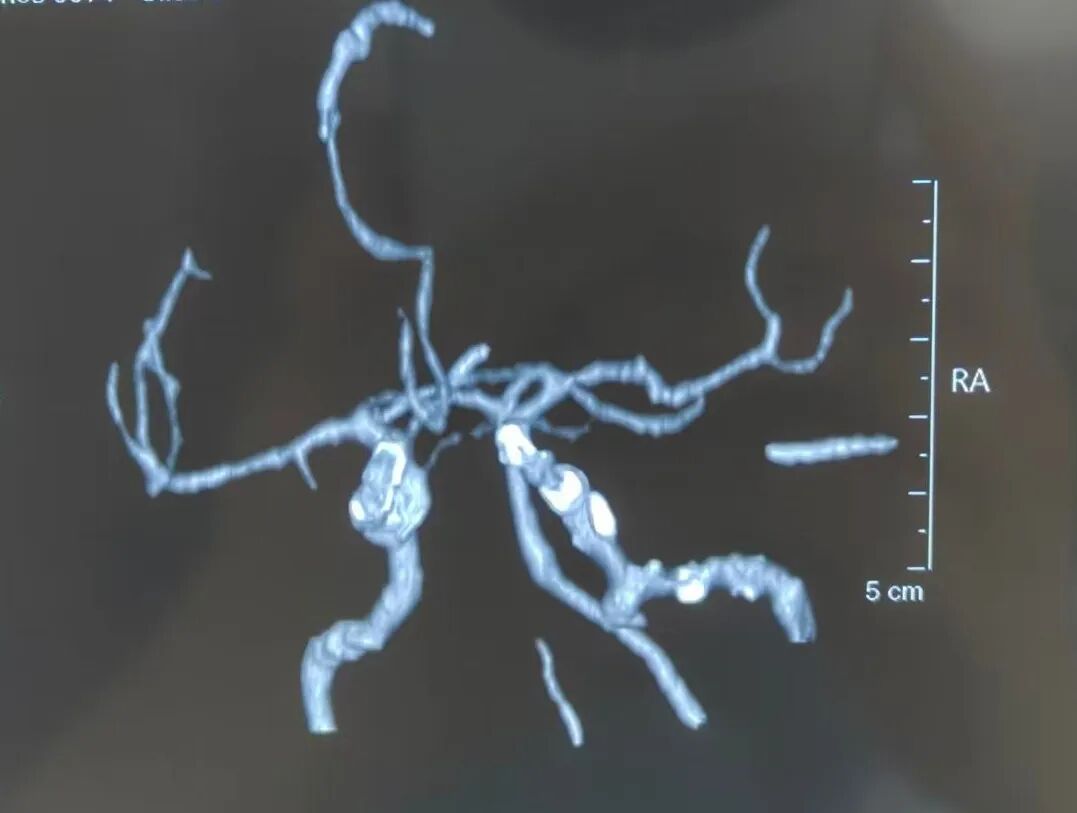

外院CTA检查:左侧颈内动脉破裂孔段假性动脉瘤形成,右侧颈内动脉起始部重度狭窄

我院CTA检查:左侧颈内动脉覆膜支架术后,假性动脉瘤消失

术前DSA:右侧颈内动脉起始段重度狭窄,左侧颈内动脉岩骨段假性动脉瘤形成

术后DSA:右侧颈内动脉支架后通畅,左侧颈内动脉岩骨段覆膜支架后假性动脉瘤消失